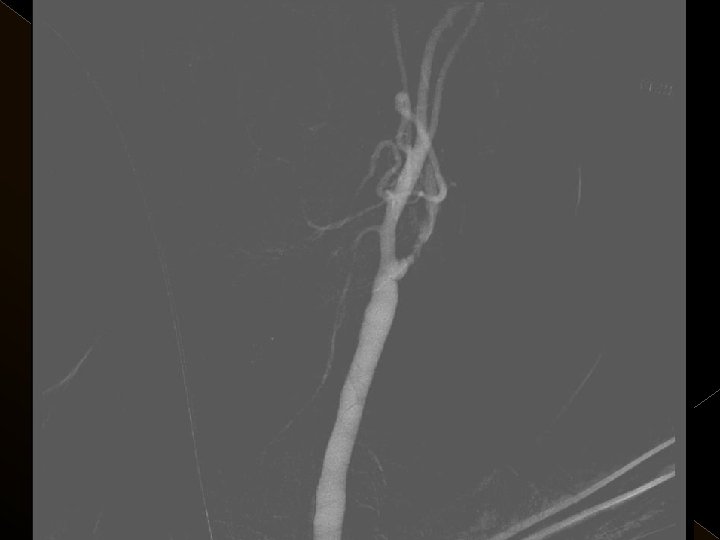

� 25 hasta (16 K, 9 E) , 27 vaskuler okluzyon � 16 orta serebral arter (MCA), � 6 baziler arter ve � 5 internal karotis arter (İCA) düzeyinde olmak üzere � Toplam 25 hasta, 27 tıkanıklığa (6 sı hariç) iv tpa sonrası endovaskuler yolla müdahale edildi

KOMPLİKASYONLAR Ponksiyon bölgesi komplikasyonları � Trombektomi stentine ait komplikasyon (*1) � Diseksiyon(*2) � Karotikokavernöz fistül (‘ 1) � Hemorajik komplikasyonlar(‘ 5) Semptomatik-nonsemptomatik � İskemik komplikasyonlar (3) � Reoklüzyon (2 i. a) � Kontrast madde nefropatisi �